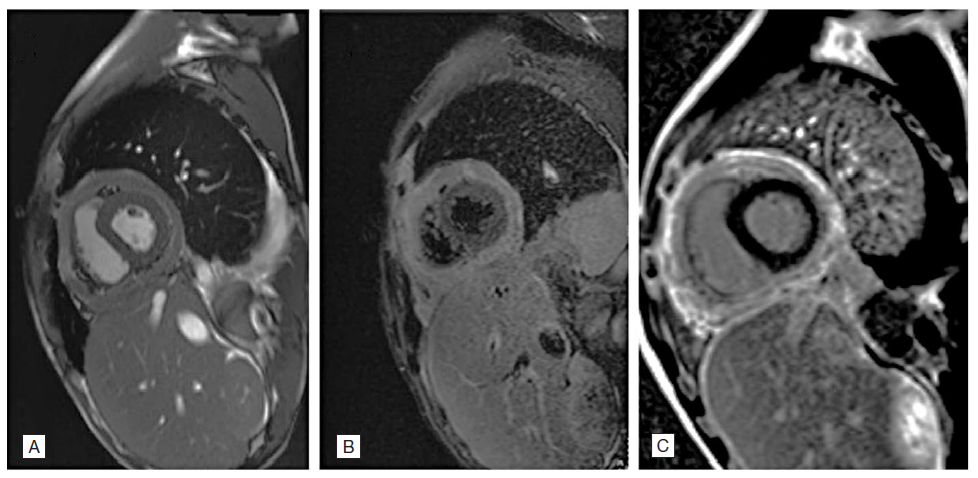

Despite targeted therapy and initial favourable progress (with a reduction in pericardial effusion seen in serial echocardiograms), on the 28th day of hospitalization, the patient developed pleuritic chest pain without relieving factors, accompanied by tachycardia and predominantly vespertine fever. This prompted repetition of the transthoracic echocardiogram (TTE), which showed a resurgence of pericardial effusion with mild to moderate fibrin deposition, pericardial effusion "swinging heart" type, with maximum expression inferoposteriorly measuring 44 mm (in the apical segment), free wall of the right ventricle measuring 39 mm, retroauricular space measuring 35 mm, and lateral space measuring 22 mm. There was slight partial collapse of the right heart chambers (systolic collapse of the right atrium and diastolic collapse of the right ventricle), with more than 25% reduction in the E wave of the mitral valve during inspiration and more than 40% reduction in the E wave of the tricuspid valve during expiration, indicating ventricular interdependence. Considering these TTE findings, an urgent pericardiocentesis was performed for diagnostic and evacuative purposes, yielding 1.150 mL of serosanguinous fluid, characterized as an exudate. The patient was started on antituberculosis therapy as well as slight compromise of overall systolic function, associated with ventricular interdependence and paradoxical movement of the interventricular septum. Given findings consistent with effusive-constrictive pericarditis, a cardiac Magnetic Resonance Imaging (MRI) was requested. The MRI revealed a non-dilated right ventricle (telediastolic volume (EDV) 79 mL, 52 mL/m2; telesystolic volume (ESV) 37 mL, 24 mL/m2; stroke volume (SV) 27 mL/m2), with preserved systolic function (ejection fraction 53%), pericardial thickening (15 mm) (Fig.1, panel A), and suggestive calcification adjacent to the right ventricle wall. Real-time imaging demonstrated septal deviation towards the right ventricle during inspiration, consistent with constrictive physiology (Fig. 1, panel C). With the diagnosis of acute constrictive pericarditis, the patient was proposed for partial pericardiectomy, (Fig. 2). At the time of discharge, he had preserved systolic function. He was reevaluated one month after the procedure, with cardiac MRI showing no evidence of constrictive physiology.

Figure 1: (A) Cardiac MRI showing pericardial thickening; (B) STIR image and T2 mapping; (C) Real-time sequence demonstrating deviation of the interventricular septum towards the right ventricle during inspiration, "septal bounce".